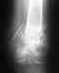

Мне 45 лет. 1,3 года назад была сделана операция-остеопластика акромиально ключичного сочленения титановой пластиной и 6 винтами. Пластина не удалена вовремя.

Я был уверен, что пластину удалять не нужно. Врачи не предупредили. Последние 3 месяца беспокоили боли в плече. Обратился за консультацией, выяснилось, что удалять пластину нужно было еще год тому назад. Врач сказал, что операция может быть очень травматичной. Нельзя ли получить больше информации о том, каковы могут быть последствия нашей общей с врачами ошибки? Насколько эта ситуация сложная? Спасибо за ответ.

Чтобы Вы могли "получить больше иинформации", надо больше информации представить - хотя бы рентгенограммы на сегодня. По невнятному описанию ситуации в нескольких строчках не уяснить, какой именно фиксатор использован, каково его состояние сейчас, насколько восстановлена анатомия надплечья, стабилен ли акромиально-ключичный сустав, блокирован ли он фиксатором, какова амплитуда движений в плечевом суставе, и т.д. и т.п.